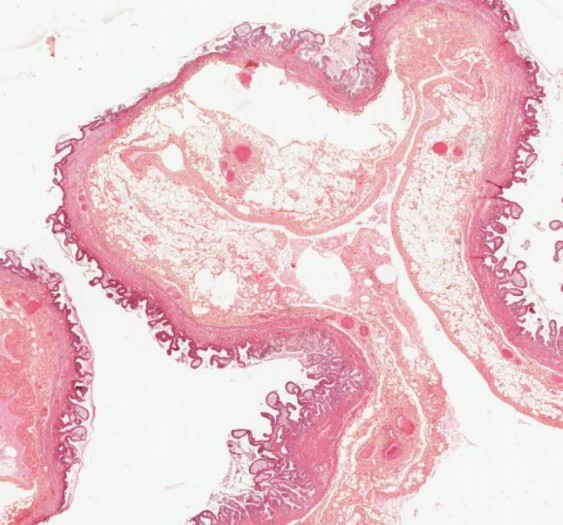

细胞和组织的适应与损伤

感染性藏毛囊肿